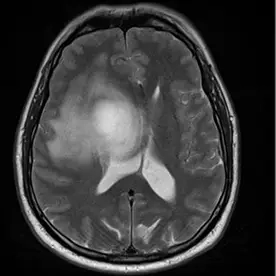

Es zeigt sich eine ausgedehnte Raumforderung des Kleinhirnbrückenwinkels rechts mit einem sogenannten "dural tail sign" (Bild 10-1, Pfeil). Die Raumforderung zeigt ein Wachstum nach intrameatal rechts (Bild 10-2, Pfeil) und entlang des Foramen ovale (Bild 10-3, Pfeil). Es zeigt sich ein ausgeprägtes verdrängendes Wachstum ohne Perifokalödem (Bild 10-4). Insgesamt passt dieses Bild zu einem Meningiom.

Typisches Bild eines Meningioms